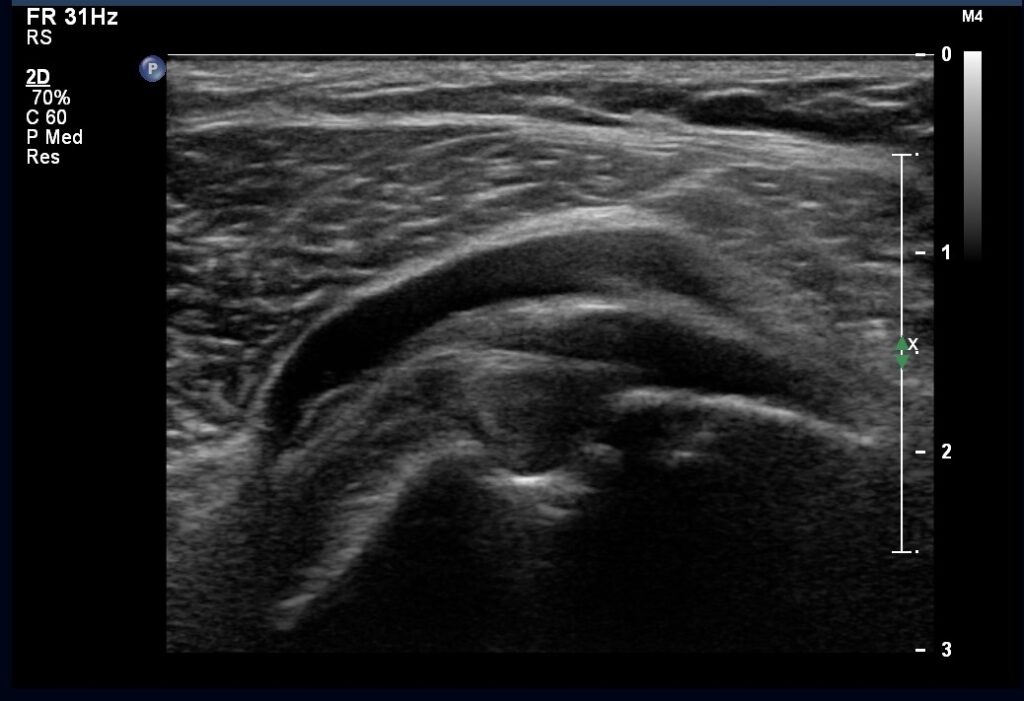

Ultrasonografia (USG)

USG to wszechstronny bohater codziennej diagnostyki. Prosty, bezpieczny, szeroko dostępny – i cholera skuteczny.

Przewaga USG w obrazowaniu tkanek miękkich

Ultrasonografia wykorzystuje ultradźwięki – fale akustyczne o tak wysokiej częstotliwości, że nie słyszysz ich uchem. Te fale rozchodzą się w Twoim ciele, odbijają się od różnych struktur, a sonda rejestruje te odbicia i tworzy obraz w czasie rzeczywistym.

To jak sonar łodzi podwodnej, tylko że służy do badania Twojego brzucha zamiast dna oceanu.

USG świetnie obrazuje narządy jamy brzusznej – wątrobę, nerki, pęcherzyk żółciowy, trzustkę. Doskonale sprawdza się też w badaniu tarczycy, piersi, naczyń krwionośnych. No i oczywiście – to królowa diagnostyki położniczej. Każda przyszła mama zna to uczucie, gdy pierwszy raz widzi swoje dziecko na ekranie USG.

Bezpieczeństwo i dostępność badania

Wiesz, co jest najlepsze? USG jest całkowicie bezpieczne. Żadnego promieniowania, żadnych szkodliwych efektów. Dlatego można je robić u dzieci, kobiet w ciąży, wielokrotnie u tej samej osoby – bez ograniczeń.

Badanie trwa zazwyczaj 15-30 minut, nie wymaga specjalnego przygotowania (no, może poza pełnym pęcherzem przy niektórych badaniach), jest bezbolesne i szeroko dostępne. To naprawdę democracja w diagnostyce – każdy ma do niego dostęp.